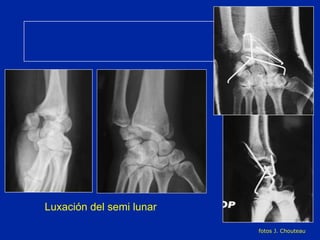

Luxación del semi lunar fotos J. Chouteau

Luxación del semi lunar  Riesgo de necrosis